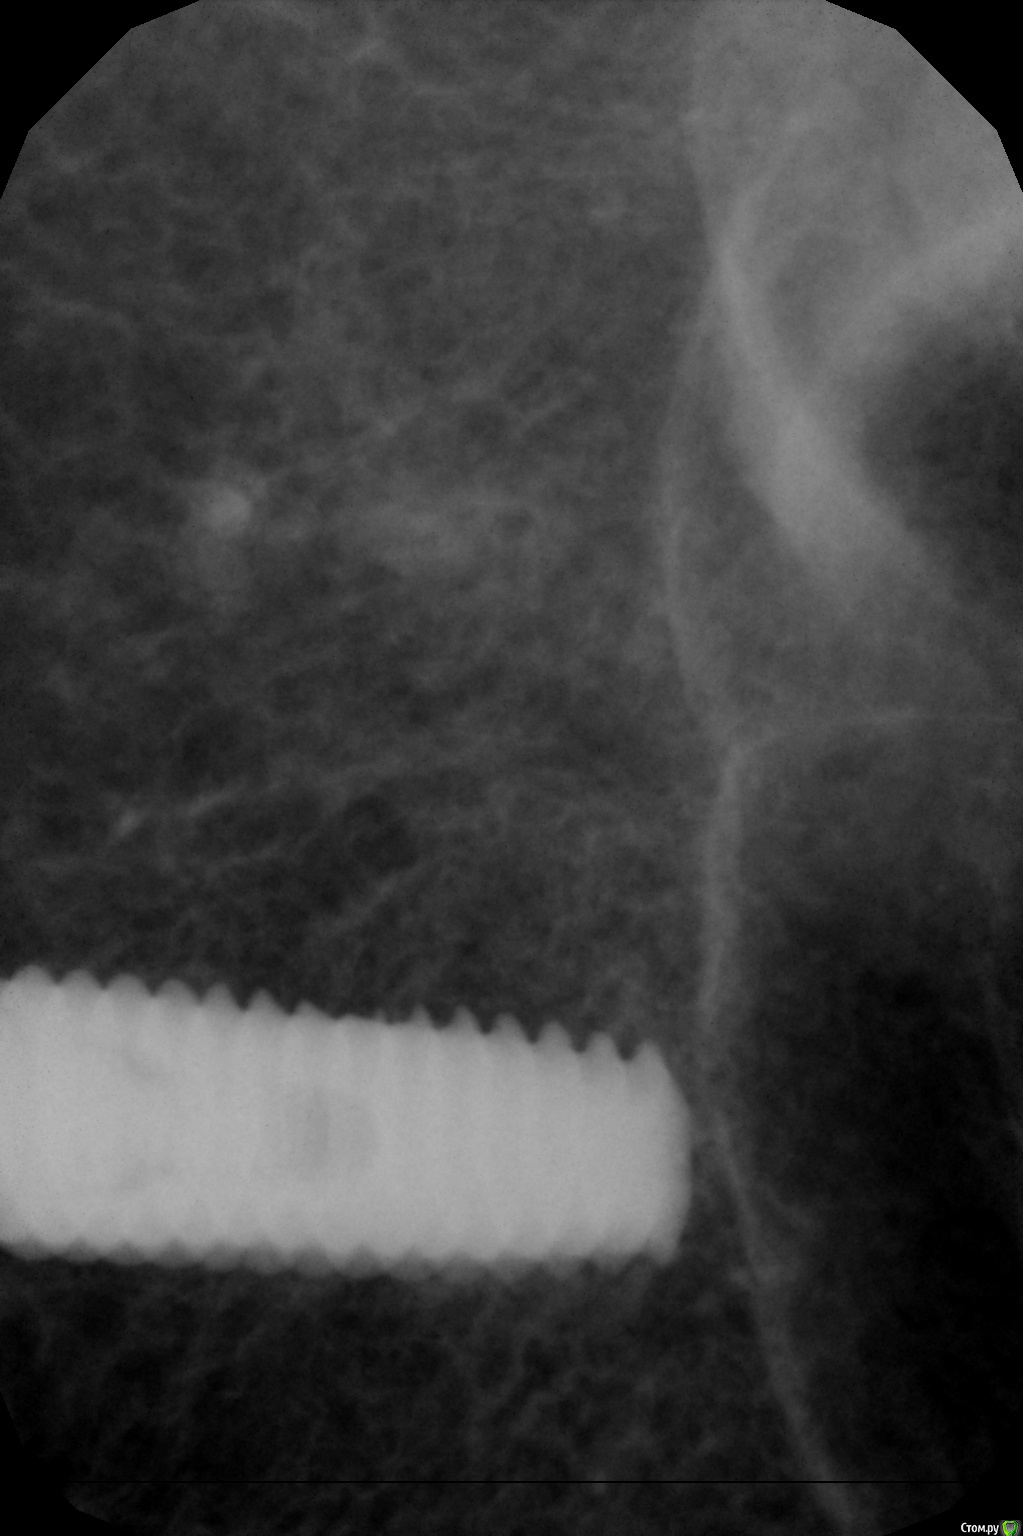

kamranchick Опубликовано 26 декабря, 2016 Автор Поделиться Опубликовано 26 декабря, 2016 По просьбе криокова.Убрал имплантат с области 17. кюретаж, ничего нет в лунке(мягких тканей итд) глубиномером все проверил, ни перфораций, ничего такого, при оказывании силы на лунку, она начинала складываться(кость)Напомню что лунку я подготовливал компресионным набором, установлен имплантат был 4.0 на 11.5ммРешил подготовить новое ложе в области 1.6.прошел пилотной фрезой 2.0 и начал сразу ставить имплантат 5.0 на 13 мм.торк - 10. или 8. решил сразу поставить формирователь. я хз блин как ложе готовить. и что надо для этого.Думаю надо было может бикортиально зафиксироваться. 1 Ссылка на комментарий